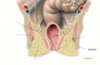

The two pelvid floor muscles: 1: _______ and 2: _________.

Muscle 1 can be split into 3: _________ , and 4: ________.

4: has different parts called _________ and ___________ / ____________.

1: Levator ani, 2: coccygeus (ischiococcygeus).

3: Illiococygeus, 4: pubococygeus.

called the puborectalis (not connected to the median raphe) and the pubovaginalis (which forms the sphincter of the vagina) /puboprostatis (wraps around the prostate).

Pubococcygeus is separated further. Purple is the puborectalis, it does a turn around motion (doesn’t attach to median raphe), this helps with angulation between anus and rectum.

The part of the pubococcygeus part forms the pubovaginalis, this forms sphincter of vagina. In the males it goes around the prostate and is called the puboprostatis.

What are the pelvic floor muscles innervated by?

Branches of pudendal nerve (S2-S4) - external anal sphincter - inferior rectal branch of pudendal.